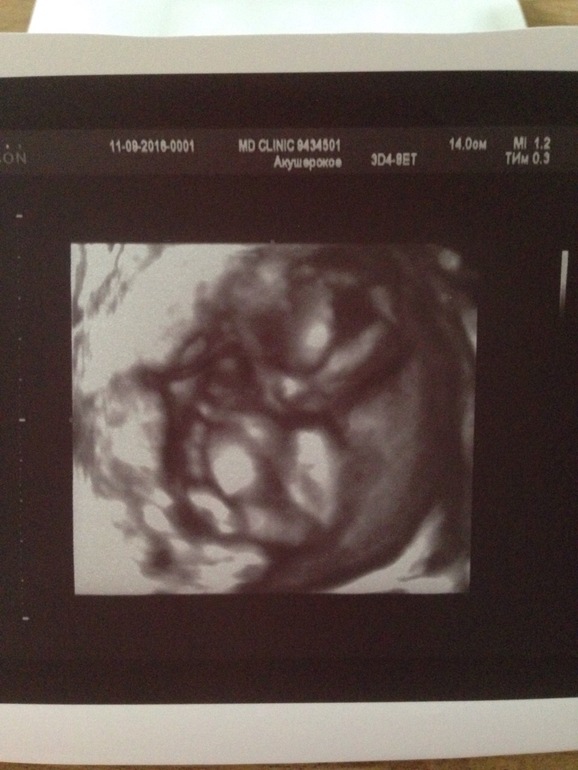

Моя малышка, кто поймёт, что и где хорошо😍😍😍 это 3 д

Малышка, да-да у нас на 200 процентов доченька, умничка, красавица растёт и радует меня. Сегодня было узи, по размерам мы чуть меньше, но это все фигня детки растут скачкообразно, сегодня меньше, а завтра в норме я не переживаю по этому поводу, тем более каких-то 2-3 дня. Вес сегодня 134 грамма. Включала врач 4д и я видела крошечку отлично в движении. Ей в пузика замечательно, занята своими важными делами😍😍😍 сосала пальчики, игралась с пуповиной, она возле шейки лежит, но не намотана. Очень долго не давала рассмотреть пол, скакала и отворачивалась 😂😂😂 но мы её поймали и увидели очередной пельмень😝😝😝💞💞💞 Вообщем все тттттттт хорошо и дай Бог так дальше и будет. А ещё мы начали пинаться вчера и сегодня чувствую частенько. Это непередаваемые чувства💞💞💞💞